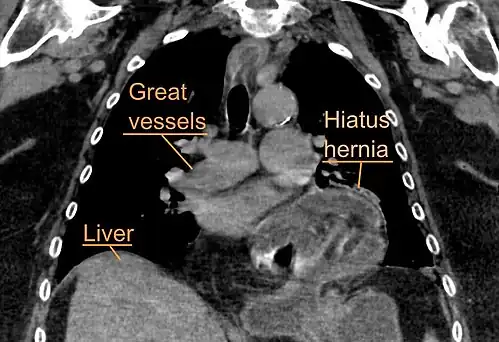

A hiatal hernia as seen on CT -

A large hiatal hernia as seen on CT imaging -